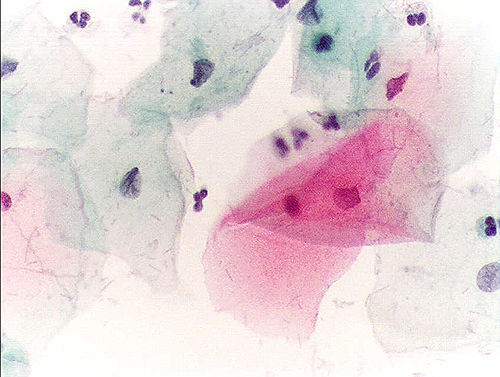

Urinalysis Sediment

Centrifuged urine sediment showing casts, crystals, and cells